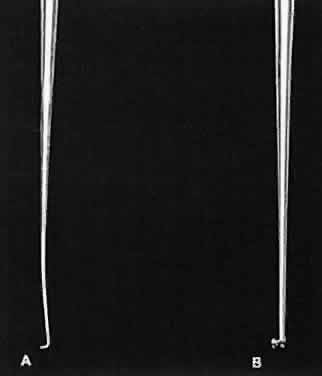

applied and may result in malfunctioning of the instrument.  Fig. 13. A surgical tie is shown on the bottom. A guide is incorporated into the

handle (arrow). The guide ensures proper alignment for the instrument to close. On the

top, a locking needle holder is shown. The lock will hold only if the

needle holder is positioned properly in the surgeon's fingertips

and the force applied is not oblique to the handle. Fig. 13. A surgical tie is shown on the bottom. A guide is incorporated into the

handle (arrow). The guide ensures proper alignment for the instrument to close. On the

top, a locking needle holder is shown. The lock will hold only if the

needle holder is positioned properly in the surgeon's fingertips

and the force applied is not oblique to the handle.